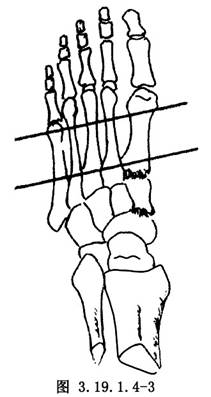

(3)前足部件的安裝:在第1~5蹠骨近側和遠側兩個平面分別經皮鑽入2枚克氏針(直徑1.0~2.0mm,平行排列),貫穿第1~5蹠骨(圖3.19.1.4-3),分別固定在兩個半環部件上,並將兩個半環用連桿連接固定成爲一個整體。